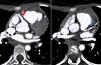

Para confirmação diagnóstica realizou Angio – TAC coronária que mostrou tronco comum da ACE com origem na vertente inferior esquerda do TAP, a cerca de 10mm da raiz da aorta (Figuras 2 e 3). Esta distância levantou dúvidas sobre a possibilidade de transferência direta da ACE para aorta. Por apresentar períodos de frequências cardíacas mais elevadas (apesar de fármaco cronotrópico negativo) e artefactos de imagem secundários a movimento, apenas foi possível definir o trajeto proximal das coronárias.

Coronariografia por TC multidetectores ‐ 64 cortes, ECG gated. Reformatações multiplanares e curvas

Tronco comum da artéria coronária esquerda com origem na vertente inferior esquerda do tronco da artéria pulmonar. O tronco comum apresenta um calibre de 2,6mm e uma extensão de cerca de 3mm, tem contornos regulares e permeabilidade preservada.

O tronco comum apresenta a normal bifurcação em artéria descendente anterior (A) e circunflexa (não dominante) (B). Estes vasos têm permeabilidade preservada na porção visualizada – sua metade proximal.